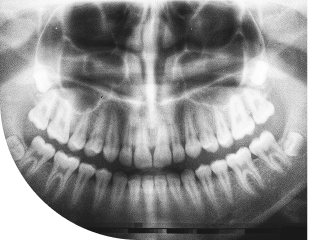

歯科医院で撮影されたパノラマレントゲン写真で、上下の歯列と顎の骨構造が一枚に写っている医療画像